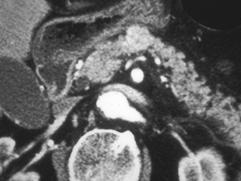

选项 A、典型症状是清晨自发性低血糖 B、是胰腺内分泌肿瘤中最常见的 C、绝大多数是恶性肿瘤 D、单发肿瘤占90%以上 E、给予葡萄糖或进餐后症状缓解

答案 C